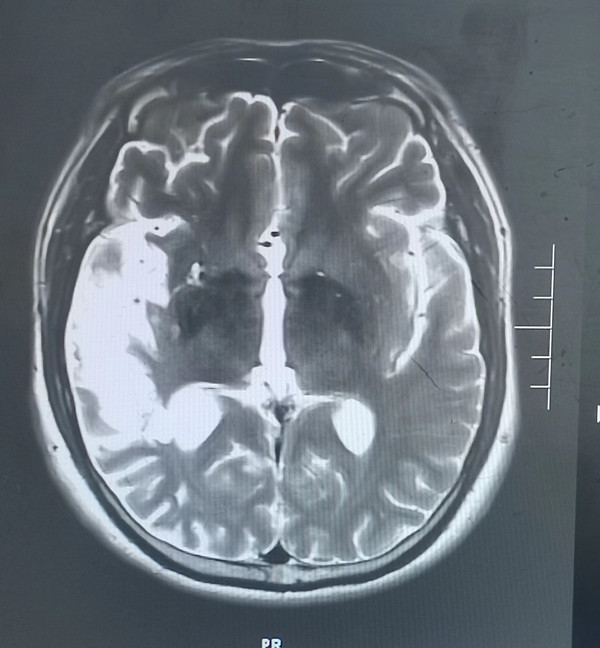

5月前46歲的徐先生因患腦梗死在西安某醫(yī)院就診,經(jīng)治療后好轉(zhuǎn),近1周再次出現(xiàn)腦梗死癥狀來我院就診,腦梗死導(dǎo)致他視野缺損,左上肢肢體無力,入院后檢查頭顱磁共振檢查發(fā)現(xiàn)右側(cè)顳葉大面積腦梗死,由于錯過溶栓機會,目前只能保守治療,徐先生一家郁悶至極,平時無高血壓、無糖尿病、高血脂等疾病,他按時服用藥物治療,他只是偶爾吸煙,為何反復(fù)出現(xiàn)腦梗死?

入院后經(jīng)追問病史患者在37歲時還患有急性心肌梗死病史,當(dāng)時急診溶栓后病情好轉(zhuǎn)。為明確患者反復(fù)出現(xiàn)腦梗死、心肌梗死原因,入院后神經(jīng)內(nèi)科張醫(yī)生為患者做了TCD發(fā)泡試驗,發(fā)現(xiàn)有明顯異常,經(jīng)食道超聲檢查發(fā)現(xiàn)患者心臟有先天性房間隔缺損。為明確患者心梗原因,我們先行冠狀動脈造影并未發(fā)現(xiàn)有嚴(yán)重冠脈狹窄病變,經(jīng)我院吳棟梁院長及崔旭輝主任介入團(tuán)隊再次評估后考慮患者屬于典型的房間隔缺損出現(xiàn)反常栓塞病案。